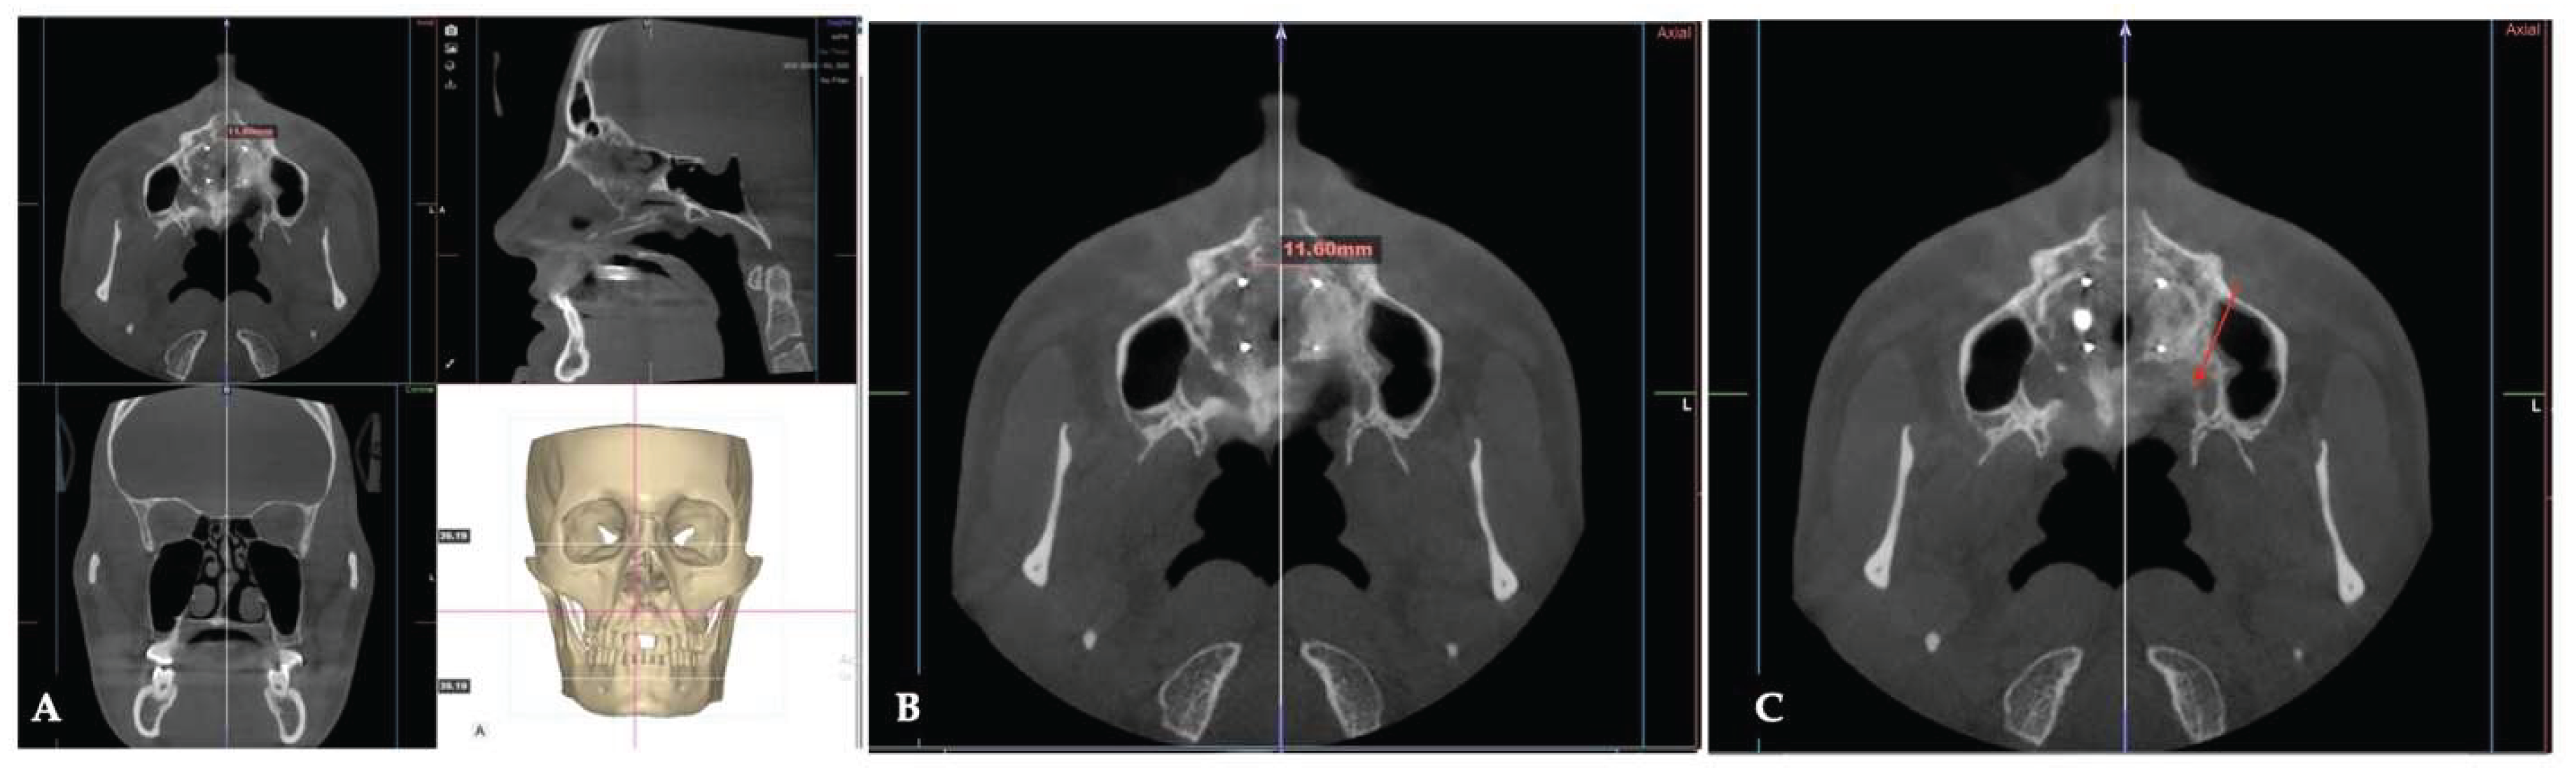

Background: While mini-screw-assisted rapid palatal expansion (MARPE) is effective for correcting maxillary transverse deficiency in adults, perimaxillary suture disarticulation—particularly at the pterygomaxillary junction—can be inconsistent. This study evaluates skeletal and dentoalveolar outcomes of a novel 3D-guided midpalatal piezocorticotomy-assisted MARPE protocol, focusing on expansion symmetry and pre-existing asymmetries. Methods: Three adult patients were retrospectively analyzed after treatment with 3D-guided midpalatal piezocorticotomy-assisted MARPE expansion and one with non-guided midpapalatal piezocorticotomy and MARPE expansion. Surgical guides were digitally designed using CBCT data to align with the nasal septum orientation in multiple planes. Perimaxillary suture disarticulation was measured pre- and post-expansion, and dentoalveolar changes were evaluated. Post-expansion asymmetries were addressed using directly printed aligners. Results: Complete midpalatal suture separation (mean 8.48 mm), involving both anterior and posterior nasal spine regions, was achieved in one patient. Bilateral pterygomaxillary disarticulation averaged 1.06–1.23 mm, resulting in forward–outward rotation of the nasomaxillary complex. Additional separation occurred at the frontonasal (2.03 mm) and vomeromaxillary (1–2 mm) sutures, with no significant changes in orbital or peri-orbital sutures. One patient presented with pre-existing dentoalveolar asymmetry, which intensified the perceived post-expansion imbalance but was successfully corrected with directly printed aligners. In the second case, 5.6 mm of suture separation resulted in a limited lateral nasal width increase (<1.5 mm), while maxillary base expansion exceeded 6 mm. A significant canine plane cant (1.2 mm) and divergent axial inclinations of the maxillary central incisors relative to the palatal plane were also observed. In the second case, a non-impactful palatal bone fracture with asymmetric displacement of the left palatine fragment was documented. After 16 months of aligner therapy, all cases exhibited favorable remodeling of the palatal structures, midpalatal suture, and alveolar processes, accompanied by improved dental alignment, occlusal plane symmetry, and mandibular dentoalveolar adaptation. The dento-alveolar expansion achieved in the third case over the course of 16 months of treatment was approximated at 4 mm. The fourth case showed consistent improvement with direct printed aligners after MARPE midpalatal diasrticulation of 11 mm after experiencing minor bone fracture. Conclusions: Human skulls exhibit considerable variability between the left and right sides, which can influence spatial balance. Pre-existing cranial asymmetries appear to be the primary contributors to asymmetry following MARPE treatment. Careful evaluation of dentoalveolar discrepancies and axial tooth inclinations is essential for preventing and managing potential asymmetric dental arch outcomes during the post-expansion phase. Although peri-maxillary bone fractures are relatively uncommon, their occurrence is influenced by multiple factors. Adjunctive techniques, such as 3D-guided midpalatal piezocorticotomy, show promise in significantly lowering the risk of intra-expansion peri-maxillary fractures.

| Suture nomenclature | Amount of disarticulation |

|---|---|

| Midpalatal | 8.48 mm |

| Palatinomaxillary (transverse) | none |

| Nasomaxillary | 1-2 mm |

| Zygomaticomaxillary | none |

| Lacrimomaxillary | none |

| Ethmoidomaxillary | none |

| Sphenomaxillary | none |

| Vomeromaxillary | 1-2 mm |

| Frontomaxillary | 2.5 mm |

| Pterygomaxillary | 1.06-1.23 mm |

| Frontonasal | 2.03 mm |

| Frontozygomatic | None |